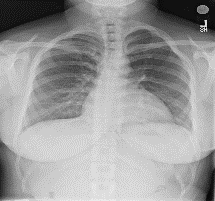

Among various medical imaging tools, chest radiographs are the most important and widely used diagnostic tool for detection of thoracic pathologies. Research is being carried out in order to propose robust automatic diagnostic tool for detection of pathologies from chest radiographs. Artificial Intelligence techniques especially deep learning methodologies have found to be giving promising results in automating the field of medicine. Lot of research has been done for automatic and fast detection of pneumothorax from chest radiographs while proposing several frameworks based on artificial intelligence and machine learning techniques. This study summarizes the existing literature for the automatic detection of pneumothorax from chest x-rays along with describing the available chest radiographs datasets. The comparative analysis of the literature is also provided in terms of goodness. Limitations of the existing literature along with the research gaps is also given for further investigation. The paper provides a brief overview of the present work for pneumothorax detection for helping the researchers in selection of optimal approach for future research.